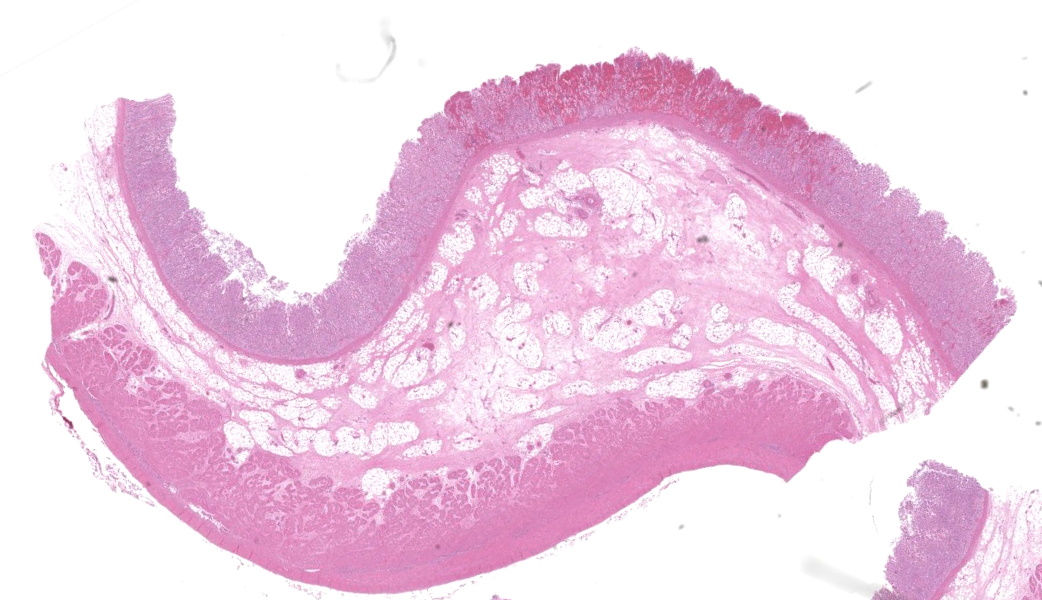

In the abomasum, focally extensive hemorrhage and edematous swelling were present in the lamina propria mucosa and in the submucosa, respectively. In the lamina propria mucosa, the capillary blood vessels and small veins showed severe congestion and hemorrhage. The endothelial cells of these vessels and arterioles had basophilic to amphophilic intranuclear inclusion bodies, of either full type or Cowdry type A. Occasionally, focal areas of necrotic mucosal epithelium were accompanied by neutrophil infiltration. In the submucosa, the endothelial cells of blood vessels had the same intranuclear inclusion bodies. Fibrinous and proteinous or serous materials were accumulated in some parts of the submucosal tissue. Neither bacteria nor fungi were detected by Gram and Giemsa stain, and by periodic acid-Schiff and Grocott methods, respectively.Contributor's Morphologic Diagnoses:

The present case was characterized pathologically by adenoviral hemorrhagic gastroenteritis and mycoplasmal caseonecrotic bronchopneumonia. The endothelial intranuclear inclusion bodies were detected histologically in the gastrointestinal tract (abomasum, duodenum, jejunum, ileum, cecum, colon, and rectum), liver, gallbladder, spleen, kidney and lung. The forestomach and brain contained no endothelial intranuclear inclusion bodies. In the abomasum, focal ulceration was associated with hemorrhagic abomasitis (No ulceration in the submitted sections). In the ileal Peyer's patch, lymphocytes were severely depleted. Epitheliotropic BAV inclusion bodies were not observed in any organs. By immunohistochemistry, the endothelial intranuclear inclusion bodies showed positive cross-reaction to anti-BAV type 7, weak cross-reaction to anti-BAV type 1, but negative for anti-BAV type 3 antisera. By transmission electron microscopy, the endothelial cells of hepatic sinusoids had paracrystalline arrays of adenovirus-like particles, 60-80 nm in diameter, in their nuclei.BAV belong to the family Adenoviridae, genera Mastadenovirus, and Atadenovirus.8 The serotypes of BAV-1, -2, -3, -9 and -10 belong to the genus Mastadenovirus, and the serotypes of BAV-4, -5, -6, -7, and -8 belong to the genus Atadenovirus.1,2,3,4,5,6,7,10 Serotypes 3, 4, 7, 10 have been associated with enteric disease.4,7,8 BAV, including serotypes 3, 7 and 10 has also been associated with respiratory disease.2,4,5,6 BAV-5 was isolated from a calf with weak calf syndrome, but not have been fully associated with severe gastroenteric disease.1

Abomasum: Abomasitis, necrohemorrhagic, acute, focally extensive, severe, with submucosal edema and endothelial intranuclear viral inclusions.JPC Comment:

This was a beautiful example of a classic entity that served as a nice little dessert to wrap the conference up. The endothelial intranuclear viral inclusions (and their ubiquitous distribution) in this case are textbook-worthy (have you ever considered how many histologic images in veterinary pathology texts come from the WSC?)As some participants struggled minimally with tissue identification in this case, a quick review of abomasal microanatomy is in order, as not all regions of the abomasum are identical. Chief and pyloric cells are only found in the fundic portion of the abomasum, whereas the pylorus and cardia lack these. Additionally, there are no goblet cells. The lack of goblet cells in this section immediately rules out large intestine, Other helpful hints include the tortuosity of gastric pits, whereas intestinal crypts are straight. Adipose tissue is not found in the intestinal submucosa but can be seen in the submucosa of the ruminant abomasum and in the equine cecum. Lastly, the degree of autolysis can also be used as a clue. The intestines tend to have a high degree of autolysis due to the milieu of bacterial flora that reside within. The stomach, on the other hand, is a borderline sterile environment that very few bacteria can tolerate due to the level of acidity (unless you are Helicobacter spp…), so there is generally little autolysis.

The contributor’s write-up of bovine adenoviruses covered much of what was discussed in conference about this ubiquitous and relevant viral family. While the pathogenesis is not well-understood, the abomasum in this case had a significant, wedge-shaped hemorrhagic infarct on the H&E slide that tied in well to the current hypothesis on the pathogenesis of this virus. It is thought that viral targeting of endothelial cells and subsequent endothelial viral inclusions may disrupt blood flow to some degree, leading to turbulence and increased incidence of thrombosis of smaller vessels that can lead to ischemic infarcts.9 There was conversation on whether this should be morphed as an abomasitis or a vasculitis due to the endothelial targeting. It was ultimately the opinion of participants that this would not classify as true vasculitis due to the lack of inflammation in vessel walls.